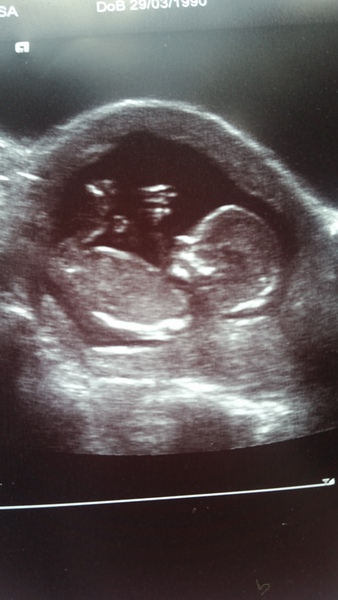

MaybeMrsMum2016 · 10/07/2015 12:02

Phiz That's a lovely scan photo. I bet you can't stop staring at it, I know I'm definitely addicted to looking at mine! Smile

Congrats on the great scan phiz

lovley scan picture phiz you can even see the toes!Smile x

Hi ladies! Just back from scan! Everything good with our lazy little jellybean. NT measured 1.9 and EDD is exactly same at 14 January.

Looks like we'll have to wait till 20wk scan for team pink or blue though as the scan is too blurry on the feet so no nub for us....

Skull wise I'm thinking boy- nub cannot tell can anyone hazard a guess?

mrschatty baby is keeping you guessing hiding it's nub and firmly keeping a central location! Wink Your picture is sooo clear and so incredibly cute, I love when you can see their little legs, feet and hands! Smile